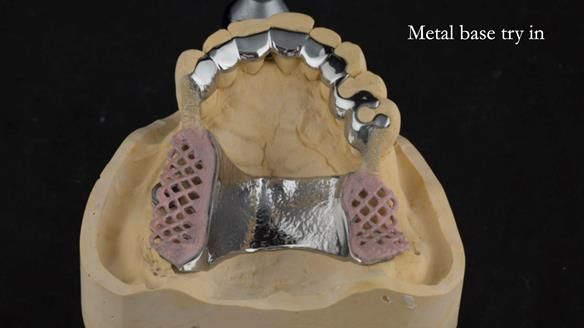

Instead, we made a Scandinavian-style, metal-based lower RPD.

A metal-based upper RPD was made,

with metal backings incorporated to future-proof the design

should further teeth fail.